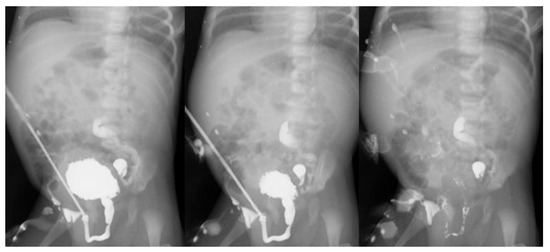

2. Case Presentation

2.1. Case 1

2.2. Case 2